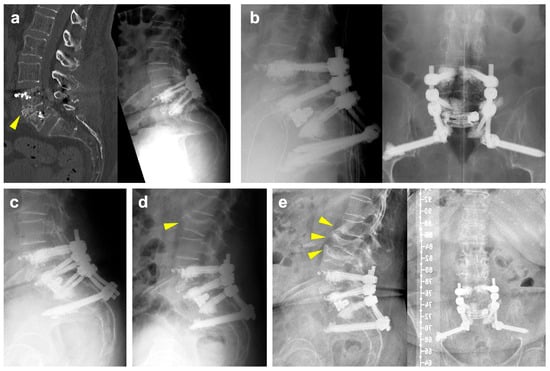

Illustrative Case

The patient is a 71-year-old female with a previous history of degenerative spondylolisthesis at L4/5 with central spinal canal stenosis and associated symptoms of spinal claudication. She therefore underwent TLIF surgery at L4/5 and bilateral decompression at L5/S1 one year prior to the current admission. At the one-year follow-up, she presented with an exacerbation of lumbar pain radiating to the right lower extremity, which was attributed to an adjacent segment degeneration at L5/S1 and a burst fracture of the L5 vertebra (Figure 1a). Clinically manifest osteoporosis with insufficiency fractures were previously known. Medical treatment with vitamin D and denosumab was previously initiated. Due to unbearable pain, revision surgery was proposed, and extension of the construct distally into the pelvis with TLIF at L5/S1 was planned. Unfortunately, the procedure had to be postponed multiple times due to episodes of cardiac decompensation. As assessed by our anesthesiologists, the preoperative CCI grade was 1 and the ASA grade was 3. Ultimately and following preoperative cardiac optimization, the intervention was performed without intraoperative complications (Figure 1b). Postoperative imaging revealed cranial cage subsidence (Figure 1c). Despite this, the patient reported a significant reduction in pain compared to preoperatively. During hospitalization, she developed anemia, which was managed with transfusion of red blood cells. Moreover, she tested positive for influenza. On postop day nine, the patient was discharged to rehabilitation.

Figure 1. (a): Preoperative CT scan (left) and standing radiographs (right) demonstrating a burst/split fracture of the L5 vertebra and cage subsidence into the lower endplate of L4 (yellow arrowhead). (b): Intraoperative lateral (left) and ap (right) radiographs following cement-augmented revision surgery involving a TLIF with an expandable interbody spacer at L5/S1 and extension of the construct to the pelvis. (c): Postoperative lateral radiographs demonstrating slight progression of cage subsidence into to L5 vertebral body. (d): Lateral radiograph following readmission showing a new fracture of the superior endplate of L2 (yellow arrowhead). (e): Lateral (left) and ap (right) radiographs at 6 months of follow-up illustrating new fractures of the lower endplate of L1, an incomplete burst fracture of L3 and progression of the L2 fracture (yellow arrowheads).

A few days after discharge, she was readmitted to cardiology due to subacute myocardial infarction and pulmonary edema. Following an episode of coughing accompanied by sudden onset of back pain, imaging revealed a new fracture of the superior endplate of L2, which did not require surgical intervention (Figure 1d). At her six-month follow-up, she reported persistent right-sided lumbar pain radiating to the buttock, although improved compared to her preoperative status. Imaging at that time showed new osteoporotic fractures at L1 and L3 (Figure 1e). Subsequently, the patient refused further follow-up at our clinic due to the long distance from her residence. She currently remains in follow-up with her general practitioner.